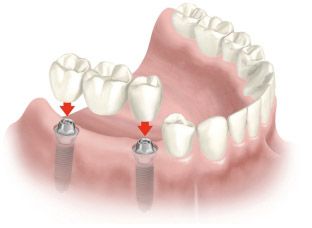

Установка моста на двух имплантатах

Зубной мост из циркония для протезирования на имплантатах